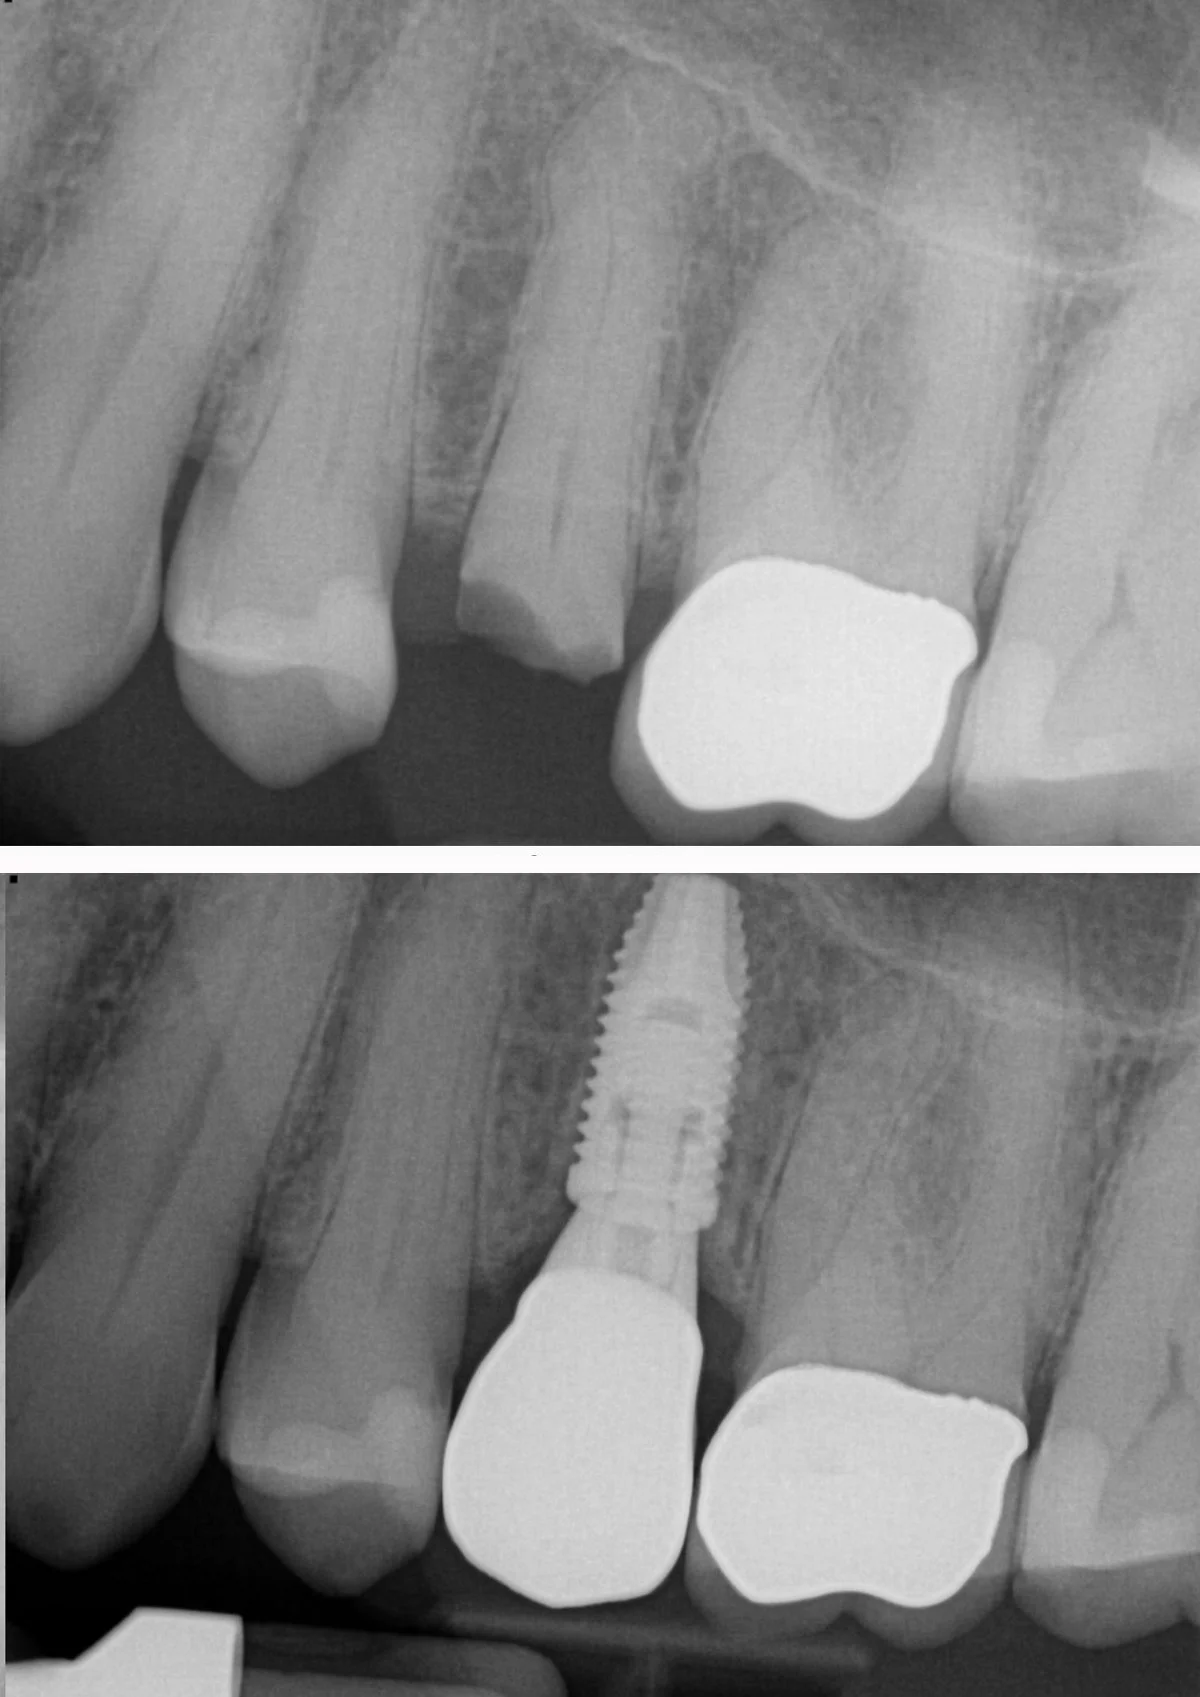

Dental Implants

With the newest technology and products, we can provide a predictable solution for tooth loss.

Implant planning

Implant placement

Extraction of tooth and placement of immediate implant

Implant Planning with CBCT imaging

Before and after implant placement of front tooth, restored with custom crown

Tooth replacement with implant and crown